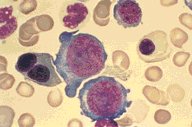

Bone Marrow Aspirate, low oil; marked erythroid

dyspoiesis, very abnormal pronormoblast cell

margins; binucleate normoblast.

This low oil view of a Wright's stained bone

marrow aspirate is from a patient with

myelodysplasia and showed marked dyspoietic

erythroid changes.